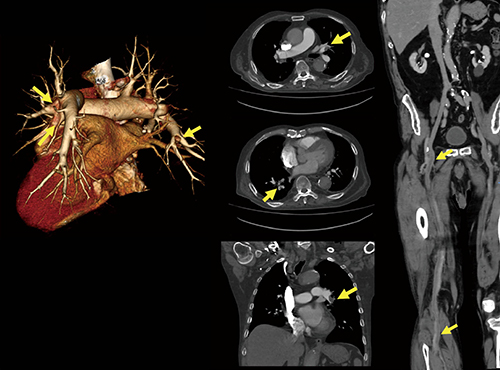

図2 肺塞栓症例

1回の造影で広範囲撮影が可能。肺塞栓および下肢静脈血栓の複数の所見を確認できた。